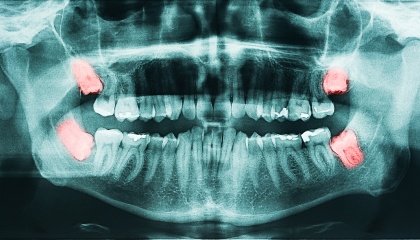

The time it takes to remove wisdom teeth depends on several factors, like the number of teeth involved and their position (erupted, partially impacted, or fully impacted). Unforeseen complications can also play a role. At Today Dental, a straightforward extraction of four wisdom teeth typically takes around 30 minutes, excluding preparation and recovery time. However, impacted or horizontal teeth may require a longer procedure.

Remember, the total time at the dental office encompasses various steps: pre-operative checkups (like consultations and x-rays), administering anesthesia or sedation, the actual extraction itself, and post-operative monitoring. During your individual consultation, your dentist or oral surgeon will provide a more accurate estimate based on your specific situation.

During your first visit, we'll delve into your medical history and have a detailed conversation about the wisdom teeth removal process. We'll take x-rays to assess the position and condition of your wisdom teeth, allowing us to create a personalized treatment plan tailored to your specific needs. This plan will outline the costs, timeline, and steps involved in the procedure. Feel free to ask any questions you may have; we're here to address any concerns you might have about the process.

The decision to remove wisdom teeth is influenced by several factors and is usually made after a comprehensive examination by your dentist at Today Dental. Wisdom teeth, also known as third molars, may need removal if they cause problems like:

- Impaction: Stuck in the jawbone and unable to erupt properly.

- Crowding: Cause other teeth to shift or become misaligned.

- Pain or pressure: Cause discomfort or pressure in the jaw.

- Infection: Become infected due to difficulty cleaning them properly.

- Damage to nearby teeth: Damage or harm surrounding teeth.